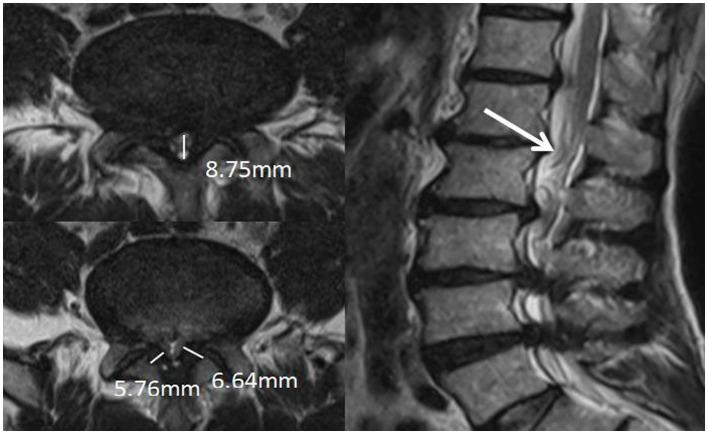

METHODS

878 patients diagnosed with LSS by clinical and MRI were divided into the redundant group (204 patients) and the nonredundant group (674 patients) according to the presence or absence of redundant nerve roots (RNRs). The anteroposterior diameter of the spinal canal (APDS) and the presence of multiple level stenosis, disc herniation, thickening of ligamentum flavum (LF) and increased epidural fat were assessed on MRI. Univariate and multivariate logistic regression analyses were performed to explore the predictors of LSS combined with RNRs.

RESULTS

Patients with LSS combined with RNRs had thicker epidural fat, smaller APDS and more combined multifaceted stenosis. Female patients and older LSS patients were more likely to develop RNRs; there was no difference between two groups in terms of disc herniation ( > 0. 05). Age, APDS, multiple level stenosis, and increased epidural fat were significantly correlated with the formation of LSS combined with RNRs ( < 0.05).

CONCLUSION

A smaller APDS and the presence of multiple level stenosis, thickening of LF, and increased epidural fat may be manifestations of anatomical differences in patients with LSS combined with RNRs. Age, APDS, multiple level stenosis, and increased epidural fat play important roles. The lumbar spine was measured and its anatomy was observed using multiple methods, and cauda equina changes were assessed to identify the best anatomical predictors and provide new therapeutic strategies for the management of LSS combined with RNRs.

方法

878例经临床及MRI诊断为LSS的患者,根据是否存在神经根冗余(RNRs)分为冗余组(204例)和非冗余组(674例)。在MRI上评估椎管前后径(APDS)以及多节段狭窄、椎间盘突出、黄韧带(LF)增厚和硬膜外脂肪增多的情况。进行单因素和多因素逻辑回归分析,以探索LSS合并RNRs的预测因素。

结果

LSS合并RNRs的患者硬膜外脂肪更厚,APDS更小,合并多节段狭窄更多。女性患者和年龄较大的LSS患者更易出现RNRs;两组间椎间盘突出情况无差异(P>0.05)。年龄、APDS、多节段狭窄和硬膜外脂肪增多与LSS合并RNRs的形成显著相关(P<0.05)。

结论

较小的APDS以及多节段狭窄、LF增厚和硬膜外脂肪增多可能是LSS合并RNRs患者解剖学差异的表现。年龄、APDS、多节段狭窄和硬膜外脂肪增多起重要作用。采用多种方法测量腰椎并观察其解剖结构,评估马尾神经变化,以确定最佳解剖学预测因素,并为LSS合并RNRs的治疗提供新策略。